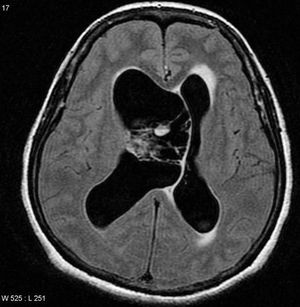

Neurocytomal image of person with abnormal seizure s, hallucinations,aphasia and epidural necrosis